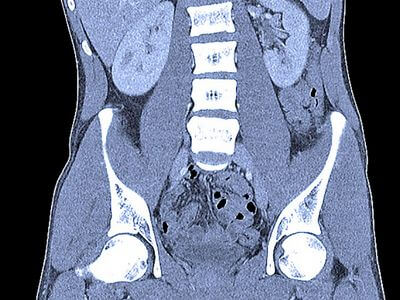

КТ може створювати детальні зображення внутрішніх органів тіла, таких як печінка, нирки, підшлункова залоза та селезінка, що допомагає лікарям діагностувати переломи кісток та пухлини. Це може допомогти лікарям діагностувати широкий спектр захворювань, включаючи рак, інфекції та запалення.

КТ особливо корисна для оцінки м’яких тканин, таких як мозок, м’язи та лімфатичні вузли. КТ може допомогти лікарям діагностувати широкий спектр захворювань, включаючи пухлини, інфекції та запалення.

КТ може виявити широкий спектр патологій, включаючи пухлини, інфекції та кісти. КТ-сканування також корисне для оцінки розміру та розташування цих аномалій, що може бути корисним при плануванні лікування.

Біль у грудях та животі

КТ можна використовувати для оцінки болю в грудях та животі, який може бути викликаний широким спектром захворювань. КТ може допомогти лікарям діагностувати такі захворювання, як пневмонія, камені в нирках та жовчному міхурі.